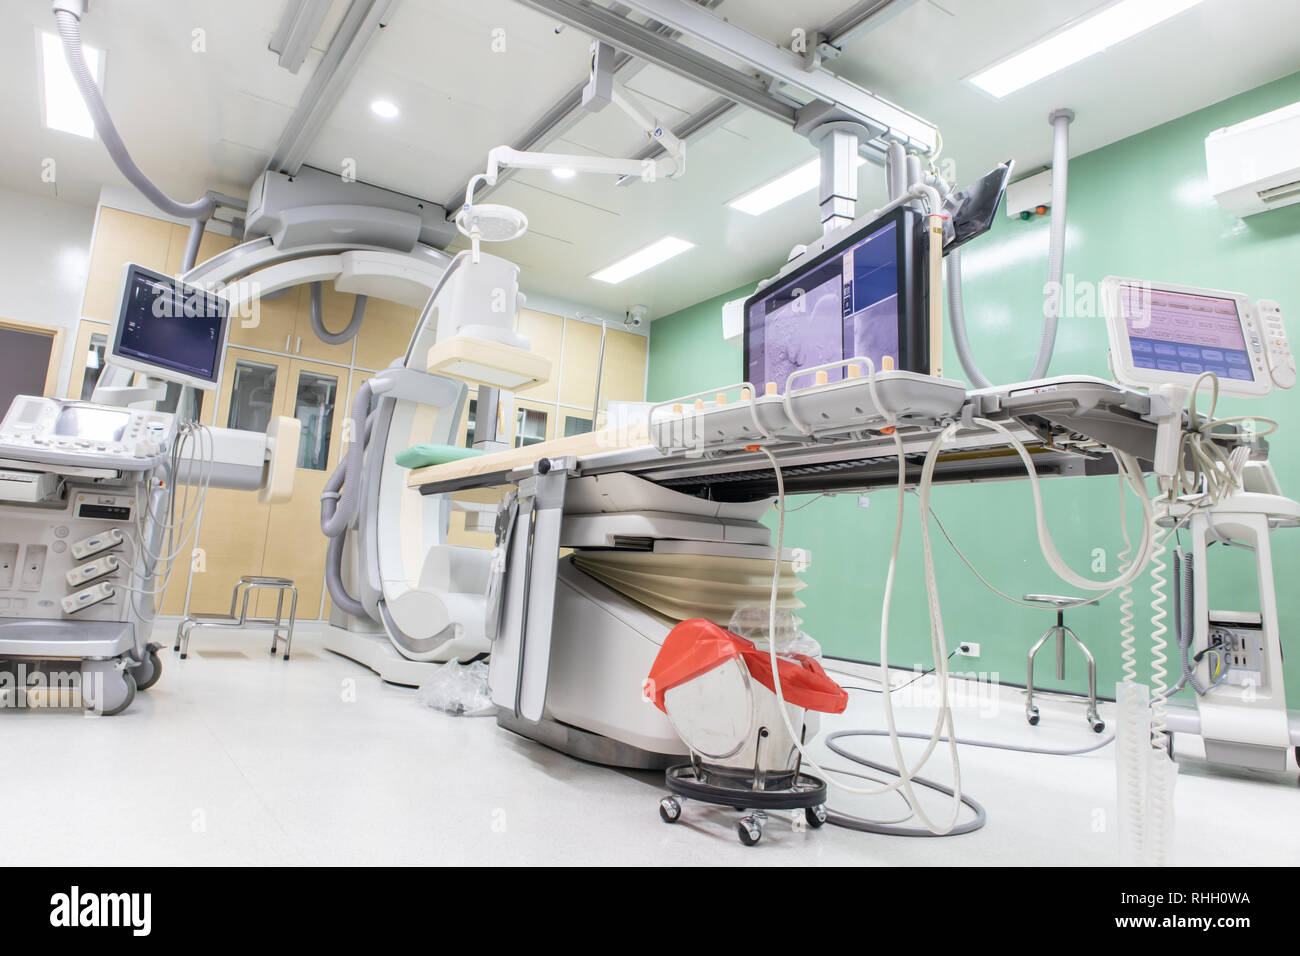

Digital Subtraction Angiography Room, DSA lab, operating room with X-ray medical scan in hospital. Stock Photohttps://www.alamy.com/image-license-details/?v=1https://www.alamy.com/digital-subtraction-angiography-room-dsa-lab-operating-room-with-x-ray-medical-scan-in-hospital-image234557835.html

Digital Subtraction Angiography Room, DSA lab, operating room with X-ray medical scan in hospital. Stock Photohttps://www.alamy.com/image-license-details/?v=1https://www.alamy.com/digital-subtraction-angiography-room-dsa-lab-operating-room-with-x-ray-medical-scan-in-hospital-image234557835.htmlRFRHH0WF–Digital Subtraction Angiography Room, DSA lab, operating room with X-ray medical scan in hospital.

Digital Subtraction Angiography Room, DSA lab, operating room with X-ray medical scan in hospital. Stock Photohttps://www.alamy.com/image-license-details/?v=1https://www.alamy.com/digital-subtraction-angiography-room-dsa-lab-operating-room-with-x-ray-medical-scan-in-hospital-image234557793.html

Digital Subtraction Angiography Room, DSA lab, operating room with X-ray medical scan in hospital. Stock Photohttps://www.alamy.com/image-license-details/?v=1https://www.alamy.com/digital-subtraction-angiography-room-dsa-lab-operating-room-with-x-ray-medical-scan-in-hospital-image234557793.htmlRFRHH0T1–Digital Subtraction Angiography Room, DSA lab, operating room with X-ray medical scan in hospital.

Digital Subtraction Angiography Room, DSA lab, operating room with X-ray medical scan in hospital. Stock Photohttps://www.alamy.com/image-license-details/?v=1https://www.alamy.com/digital-subtraction-angiography-room-dsa-lab-operating-room-with-x-ray-medical-scan-in-hospital-image234557799.html

Digital Subtraction Angiography Room, DSA lab, operating room with X-ray medical scan in hospital. Stock Photohttps://www.alamy.com/image-license-details/?v=1https://www.alamy.com/digital-subtraction-angiography-room-dsa-lab-operating-room-with-x-ray-medical-scan-in-hospital-image234557799.htmlRFRHH0T7–Digital Subtraction Angiography Room, DSA lab, operating room with X-ray medical scan in hospital.

Digital Subtraction Angiography Room, DSA lab, operating room with X-ray medical scan in hospital. Stock Photohttps://www.alamy.com/image-license-details/?v=1https://www.alamy.com/digital-subtraction-angiography-room-dsa-lab-operating-room-with-x-ray-medical-scan-in-hospital-image234557821.html

Digital Subtraction Angiography Room, DSA lab, operating room with X-ray medical scan in hospital. Stock Photohttps://www.alamy.com/image-license-details/?v=1https://www.alamy.com/digital-subtraction-angiography-room-dsa-lab-operating-room-with-x-ray-medical-scan-in-hospital-image234557821.htmlRFRHH0W1–Digital Subtraction Angiography Room, DSA lab, operating room with X-ray medical scan in hospital.

Digital Subtraction Angiography Room, DSA lab, operating room with X-ray medical scan in hospital. Stock Photohttps://www.alamy.com/image-license-details/?v=1https://www.alamy.com/digital-subtraction-angiography-room-dsa-lab-operating-room-with-x-ray-medical-scan-in-hospital-image234557830.html

Digital Subtraction Angiography Room, DSA lab, operating room with X-ray medical scan in hospital. Stock Photohttps://www.alamy.com/image-license-details/?v=1https://www.alamy.com/digital-subtraction-angiography-room-dsa-lab-operating-room-with-x-ray-medical-scan-in-hospital-image234557830.htmlRFRHH0WA–Digital Subtraction Angiography Room, DSA lab, operating room with X-ray medical scan in hospital.